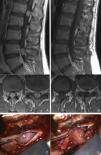

Material y métodosEstudio retrospectivo de 29 pacientes con 30 lesiones espinales intradurales extramedulares abordados mediante laminectomía unilateral microquirúrgica —hemilaminectomía—. Fueron evaluados datos epidemiológicos, localización e histología de las lesiones y evolución clínica y radiológica de los pacientes. La escala Nurick fue utilizada para la valoración funcional pre y postoperatoria realizada en la última revisión de seguimiento. La edad media de los pacientes era de 60 años, con predominio del sexo femenino. El tiempo medio de evolución clínica preoperatoria fue de 11,6 meses, y los síntomas sensitivos y motores fueron los más frecuentes. El diagnóstico histológico más común fue meningioma, seguida de neurinoma y ependimoma. El nivel más frecuente afectado fue el dorsal, seguido del lumbar y del cervical.

ResultadosLa resección total fue posible en todos los casos excepto en un neurinoma cervical con extensión extraforaminal. Tres pacientes presentaron complicaciones postoperatorias —fístula de líquido cefalorraquídeo, seudomeningocele asintomático y empeoramiento funcional postoperatorio— que se resolvieron mediante tratamiento conservador. El tiempo medio de seguimiento clínico y radiológico fue de 33,4 meses, sin que se observara recidiva de la lesión excepto en 2 pacientes con meningiomas que recurrieron tardíamente. Al finalizar dicho periodo, los pacientes sin trastorno funcional preoperatorio permanecían estables, y todos los pacientes con trastorno funcional habían presentado mejoría de al menos un punto en la escala de Nurick.

Materials and methodsThis was a retrospective study of 29 patients with 30 extramedullary, intradural spinal tumours approached through unilateral laminectomy —hemilaminectomy. Epidemiological data, location and histology of the lesions and radiological and clinical evolution of the patients were recorded. The Nurick scale was used in the preoperative and postoperative functional assessment conducted during the last follow-up consultation. The mean age of patients was 60 years and there was a predominance of the female gender. The mean time elapsed from the onset of symptoms to diagnosis was 11.6 months. Sensitive and motor deficits were the most common symptoms. Meningioma was the most frequent lesion, followed by neurinoma and ependymoma. The most commonly affected level was the dorsal, followed by the lumbar and cervical.

ResultsTotal resection was performed in all cases except for one cervical neurinoma with extraforaminal extension. Three patients presented postoperative complications —cerebrospinal fluid fistula, asymptomatic pseudomeningocele and postoperative functional worsening— which were resolved with conservative treatment. The mean time of clinical and radiological follow-up was 33.4 months, with no tumoural recurrences being observed except for two cases of meningiomas. After the follow-up period, patients without functional disorders remained stable and all patients with functional disorders presented a clinical improvement of at least one point in the Nurick scale.